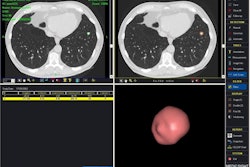

![]() |

| Above: A 7-mm nodule in right middle lobe, representing a true-positive CAD finding. Below: A 5-mm nodule in the lower right lobe, representing a true-positive CAD finding. |